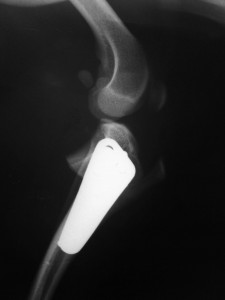

- Chirurgie

- Lahmheit

- „Spezialitäten“

- Ausgewählte Operationen

unsere „Spezialitäten“ - Offizielle Untersuchungen